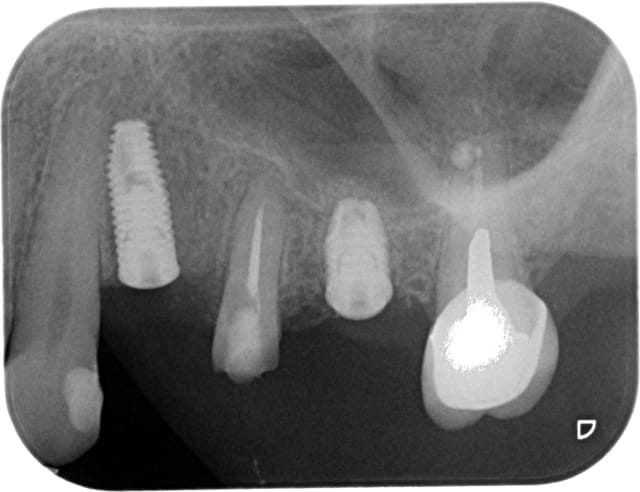

Voila je me lance, mais je n'ai que les RX.

24: largeur de crete 3mm, hauteur 9.8, j'ai placé un 3.75x10

26: largeur de crete 4mm, hauteur 4.7, j'ai placé un 4.2x7

A vos critiques et au plaisir de vous lire.